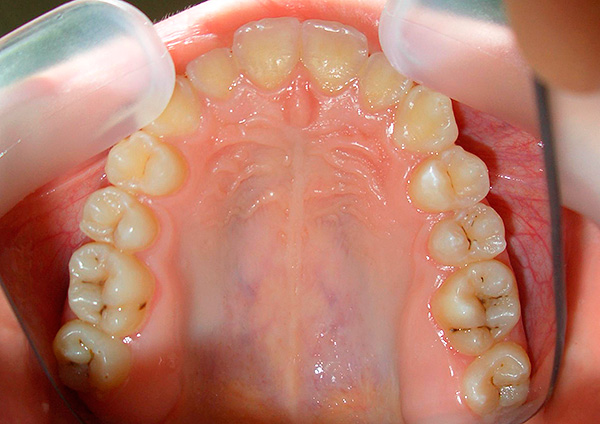

Il danno alla carie dello smalto delle superfici di contatto negli spazi dentali è l'opzione più insidiosa per lo sviluppo della patologia. A causa del lungo corso nascosto del processo distruttivo tra i denti, esiste la probabilità di una diagnosi tardiva della lesione e della sua transizione allo stadio della carie della dentina, una forma più grave del processo patologico.